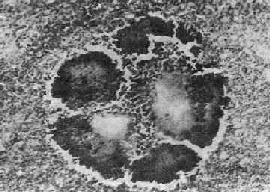

图18-36 放线菌病 病灶中的“硫黄颗粒”,周围部分菌丝排列成放线状。菌丝末端膨大呈棒状 有时组织切片中菌丝不明显,可作革兰染色,放线菌菌丝体为革兰阳性,胶样鞘为革兰阴性,据此可确诊为放线菌病。 放线菌病常同时合并其他细菌感染。病变常迁延不愈。一处病变纤维化,附近可出现新的病灶,再形成脓肿。日久后可引起大量组织破坏和瘢痕形成。颈面部放线菌病最多见,约占放线菌病总数的一半。病原菌常在口腔粘膜损伤(如拨芽等)时侵入。病变多发生在颌骨附近。早期,牙龈及邻近软组织肿胀、质硬、表面皮肤暗红色,以后液化形成脓肿。病变向周围组织扩展,形成多数脓肿,彼此沟通形成窦道,并常穿破皮肤形成瘘管。病变并可侵犯颌骨引起骨膜炎和骨髓炎,严重者可进一步扩展到颅骨、脑膜及脑。 腹内放线菌病多发生于阑尾和结肠,在粘膜下层形成小脓肿。病变常穿透肠壁引起局限性腹膜炎,并可侵入邻近肠袢、腹膜后组织和腹壁,形成排脓的窦道。有时并可通过淋巴管或血道、或直接蔓延到肝引起多发性肝脓肿,进一步可引起膈下脓肿,最后可破入胸腔引起胸腔内感染。感染也可沿腰肌蔓延到肾周围组织和腰椎,并可引起腰肌脓肿。 胸内放线菌病因吸入放线菌引起,或由腹部放线菌病蔓延而来,常形成肺脓肿,逐渐扩散可形成肺胸膜瘘或脓胸。进一步可侵犯胸壁及肋骨,引起胸壁瘘管。有时可蔓延到心包引起化脓性心包炎。

五、放线菌病放线菌病(actinomycosis)主要是以色列氏放线菌(actinomyces israeli)引起的一种慢性化脓性炎症。根据现代的生物学分类,放线菌不属于真菌而属于一种厌氧细菌。由于它所引起的病变与霉菌病相似,以及按照过去的习惯,通常仍将放线菌病与真菌病一起叙述。放线菌有细胞壁,其化学成分与细菌相似,没有核膜。菌体呈细丝状,与真菌相似,菌丝的粗细与普通杆菌相似,一般直径不超过1μm。菌丝分支,可断裂为杆状。放线菌的种类很多。在自然界分布极广,空气、土壤、水源中都有放线菌存在。少数菌株对人类有致病性,其中最主要的为以色列氏放线菌。以色列氏放线菌是人口腔正常菌群中的腐物寄生菌,在拨牙、外伤或其它原因引起口腔粘膜损伤时,放线菌可由伤口侵入。也可通过吞咽或吸入带菌物质进入胃肠或肺。因此放线菌病主要发生于颈面部和胸腹器官。 【病理变化】 放线菌病和病变为慢性化脓性炎症。局部组织水肿,有大量中性粒细胞和单核细胞浸润,其间逐渐出现许多大小不等的坏死区,形成多数小脓肿,周围纤维组织增生。脓肿大小不等,常相互融合,并向邻近组织蔓延,形成许多窦道和瘘管。脓肿壁和窦道周围肉芽组织内有大量中性粒细胞、淋巴细胞和单核细胞浸润,有时并有少数多核巨细胞,部分可见大量吞噬脂类的巨噬细胞,因此肉眼观常带黄色。放线菌在脓肿壁、窦道壁和脓腔内繁殖,形成菌落。有时肉眼可见脓液内有细小的黄色颗粒,直径约1~2mm,称为“硫黄颗粒”。取硫黄颗粒直接压片或在组织切片中可见颗粒由分支的菌丝交织而成。在HE染色的组织切片中,颗粒中央部分染蓝紫色,周围部分菌丝排列成放线状,菌丝末端常有胶样物质组成的鞘包围而膨大呈棒状,染伊红色,所以称为放线菌(图18-36)。